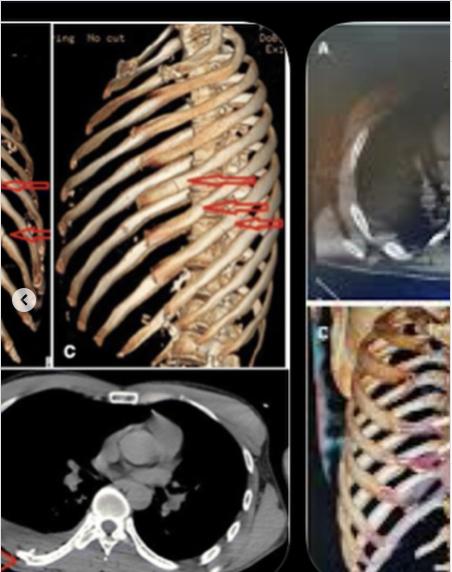

A través de sus redes sociales, el hijo mayor de Rick Harrison difundió crudas imágenes de su rostro golpeado y las radiografías que confirman la gravedad del impacto: tiene 11 fracturas.